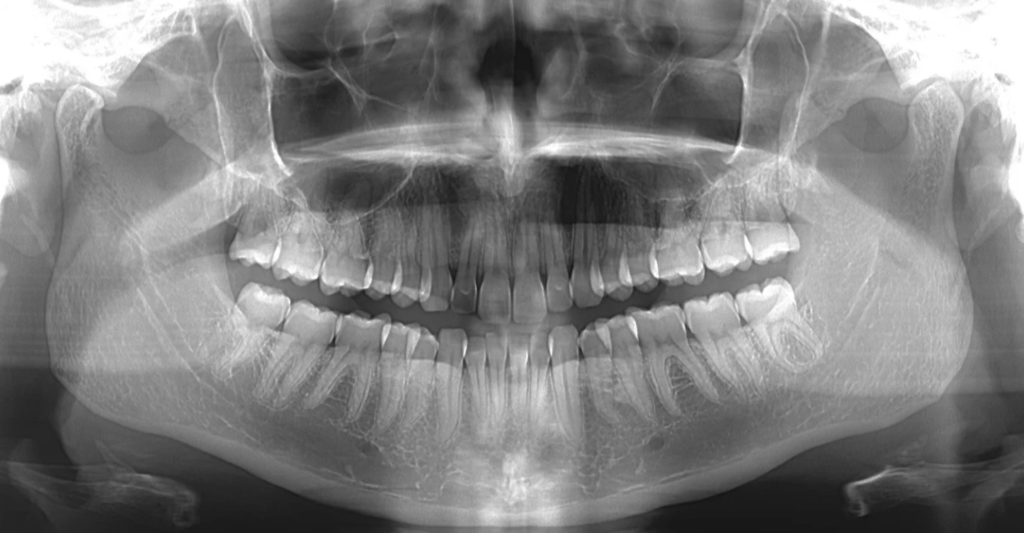

根管の形状は非常に複雑で、通常のレントゲン写真では完全に把握することができません。従来のレントゲンは二次元の画像であるため、根管の立体的な構造や分岐を正確に捉えることができないのです。

歯科用CT(コーンビームCT)は、歯の三次元的な構造を詳細に撮影できる装置です。これにより、複雑な根管形態や通常のレントゲンでは発見できない病変を事前に把握することができます。

私が日々の診療で実感するのは、CTを使用することで治療前の診断精度が格段に向上するということです。例えば、レントゲンでは見えなかった副根管や複雑な湾曲が明確に確認でき、それに応じた治療計画を立てることができます。

CTを導入している歯科医院は、精密な診断と治療にこだわりを持っている証拠です。根管治療を受ける際は、歯科用CTを活用しているかどうかも重要なチェックポイントとなります。